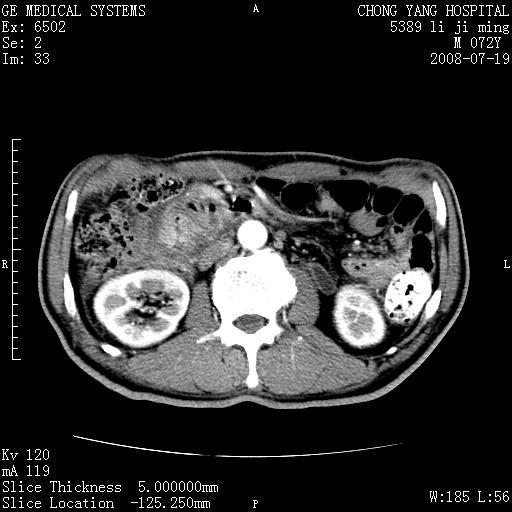

以下是引用zjzjr在2008-7-19 20:57:00的发言:[br]胰头增大,边缘模糊,周围可见渗出影,右侧肾前筋膜增厚.支持胰腺炎.

以下是引用yangyudong333在2008-7-20 6:56:00的发言:[br]胰腺增大尤以胰头明显,边缘模糊,周围可见渗出影,右侧肾前筋膜增厚,肠管於涨.支持胰腺炎

以下是引用不学无术在2008-7-19 23:15:00的发言:[br]胰腺增大尤以胰头明显,边缘模糊,周围可见渗出影,右侧肾前筋膜增厚,肠管於涨.支持胰腺炎